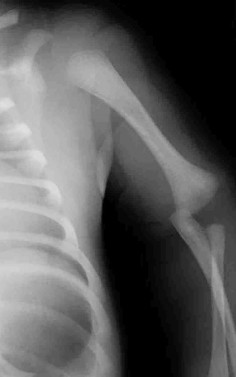

A 9-year-old male presents with acute shoulder pain after throwing a baseball. Radiographs reveal a pathologic fracture through a centrally located, lytic, expansile bone lesion in the proximal humeral metaphysis. A "fallen leaf" sign is noted. What is the most appropriate initial management?

Explanation